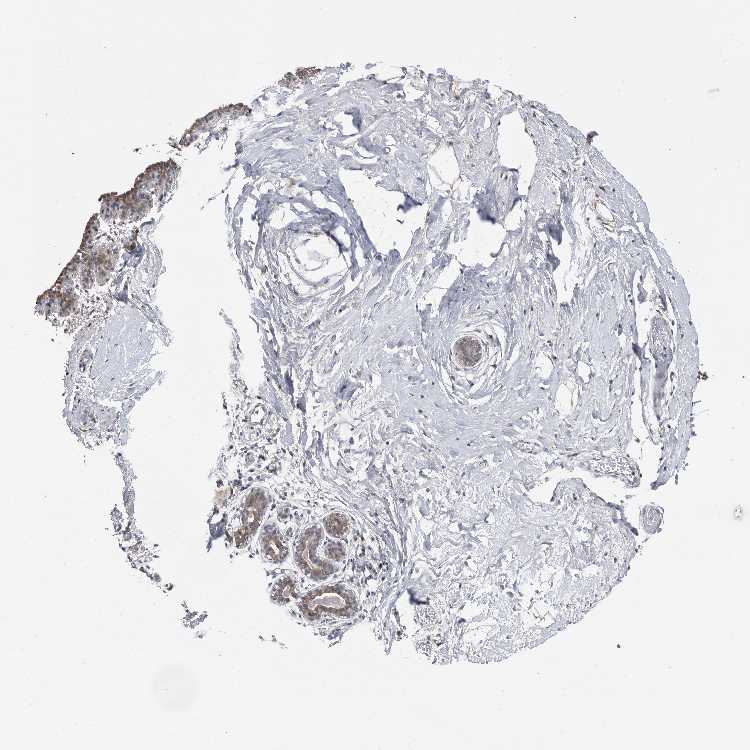

BREAST - Antibody stainingi

Antibody staining in the annotated cell types in the current human tissue is reported as not detected, low, medium, or high, based on conventional immunohistochemistry profiling in selected tissues. This score is based on the combination of the staining intensity and fraction of stained cells.

Each image is clickable and will lead to virtual microscopy that enables deeper exploration of all samples and also displays staining intensity scores, fraction scores and subcellular localization as well as patient and tissue information for each sample.

Antibody HPA030196Antibody HPA030197Antibody HPA030198Antibody CAB033918

Adipocytes LowLowMediumLow

Glandular cells MediumNot detectedHighLow

Myoepithelial cells Not detectedNot detectedNot detectedLow